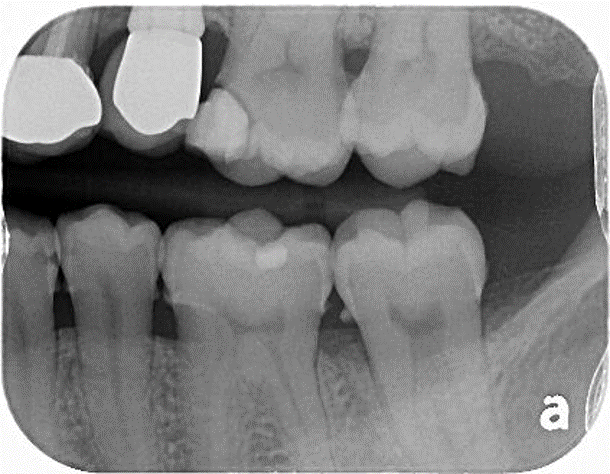

二次蛀牙

將牙齦下蛀牙移除並預填補